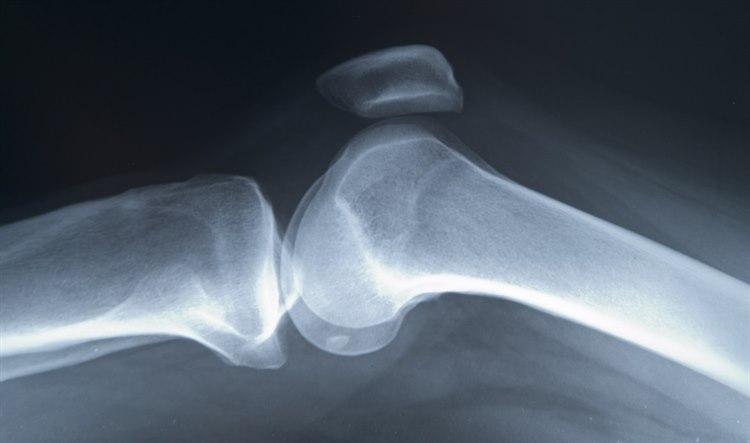

Knoklene

Knoklene i kroppen deles inn i fire kategorier:

Rørknokler. Disse knoklene har et langt rørformet skaft (diafysen) og to bredere ender (epifysene). Skaftet består av et hulrom som er dekket av kompakt beinvev. Hos barn og unge består dette hulrommet av rød beinmarg som produserer blodceller. Hos voksne er beinmargen her blitt gul og deltar ikke i produksjonen av blodceller. Eksempler på rørknokler er beinene i låret, leggen, overarmen og underarmen.